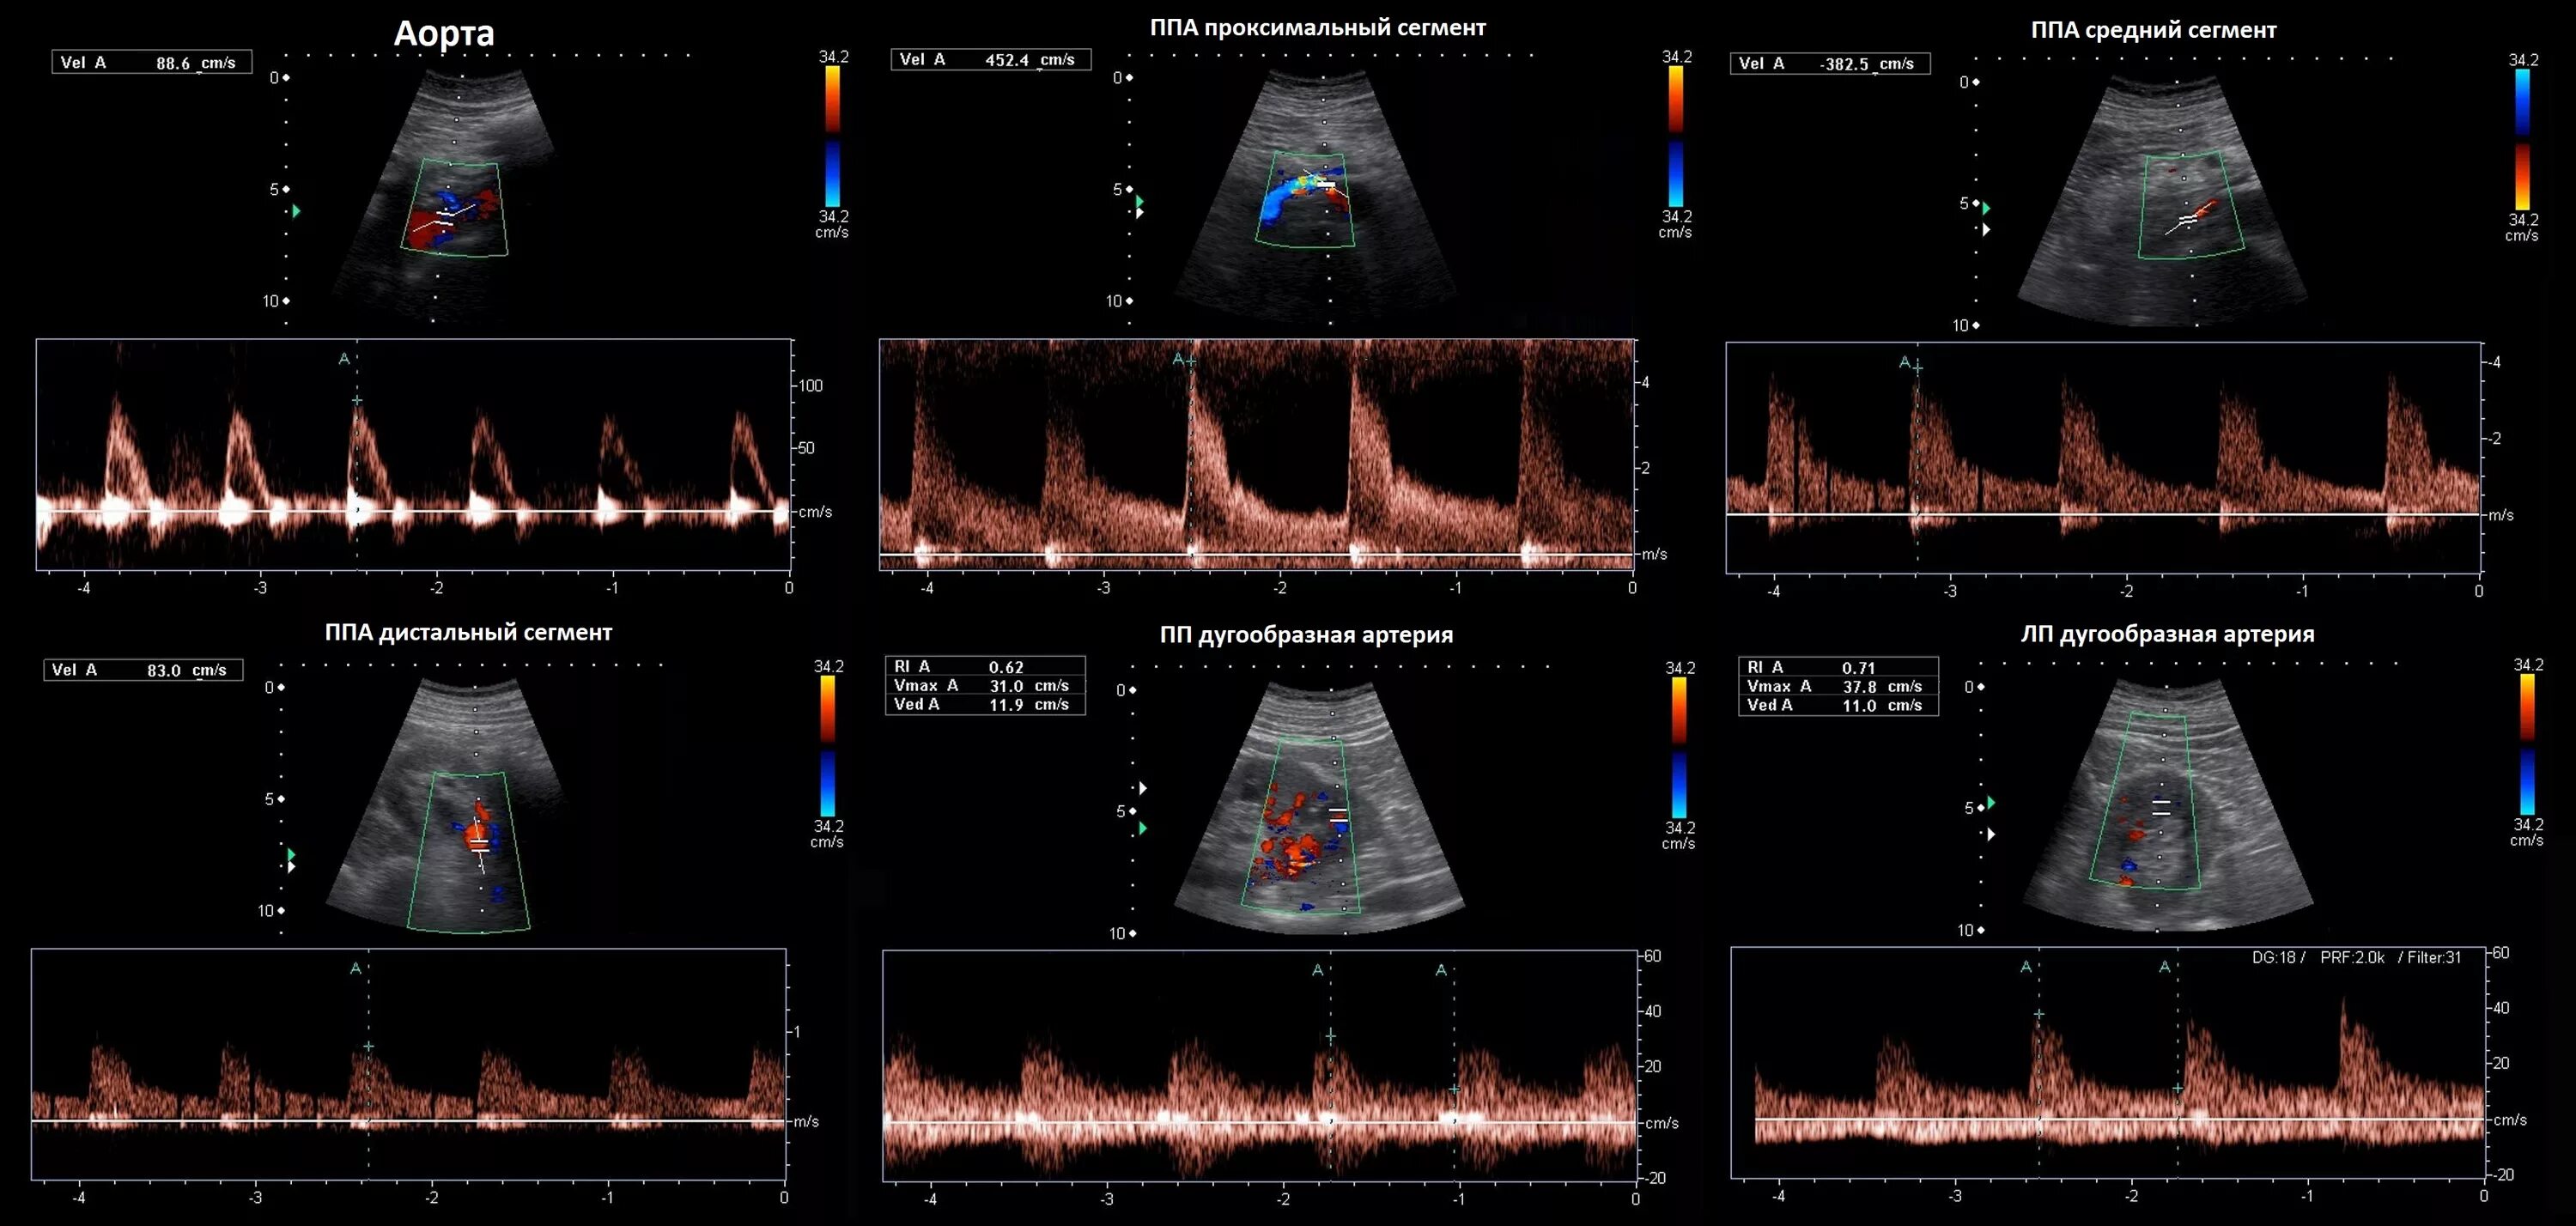

Тип кровотока 1 типа